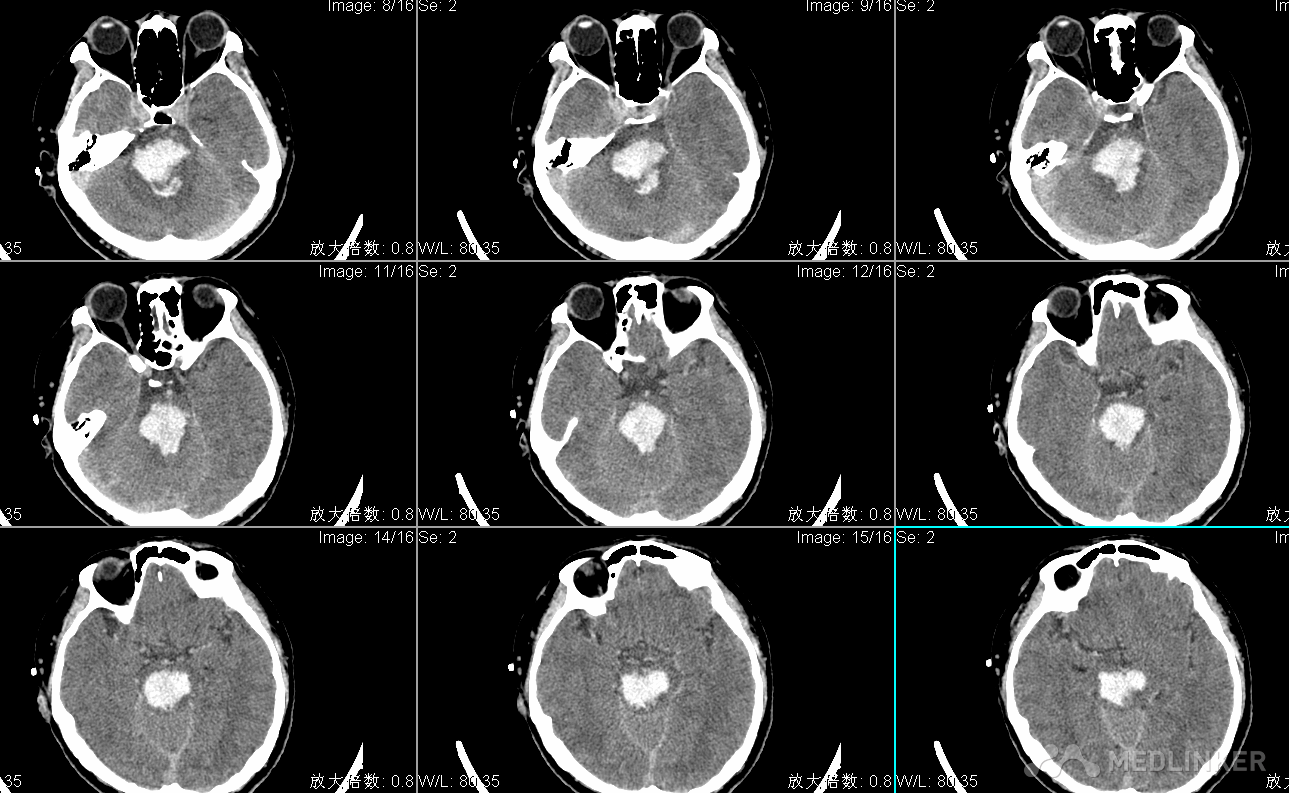

查体:T:36.3℃ P:73次/分R: 20次/分BP:154/107mmHg 嗜睡状态,呼之睁眼,应答切题,四肢可从嘱活动,GCS14分,双侧瞳孔直径左:右=2:2mm,光反射灵敏,可及水平眼震,额纹对称,颈软,左侧肢体4级,右侧肢体肌力5级,肌张力不高,腱反射(++),生理反射存在,双巴氏征(-)。入院头CT显示脑桥出血出血量约2ml。

入院诊断为:1.脑干出血 2.高血压病3级(极高危)3.吸入性肺炎。 入院后给予止血、控制血压及对症支持治疗,患者病情进行性加重,昏迷,四肢刺激强直,自主呼吸消失,复查头CT显示脑干出血多田公式计算约20ml,家属强烈要求手术治疗。